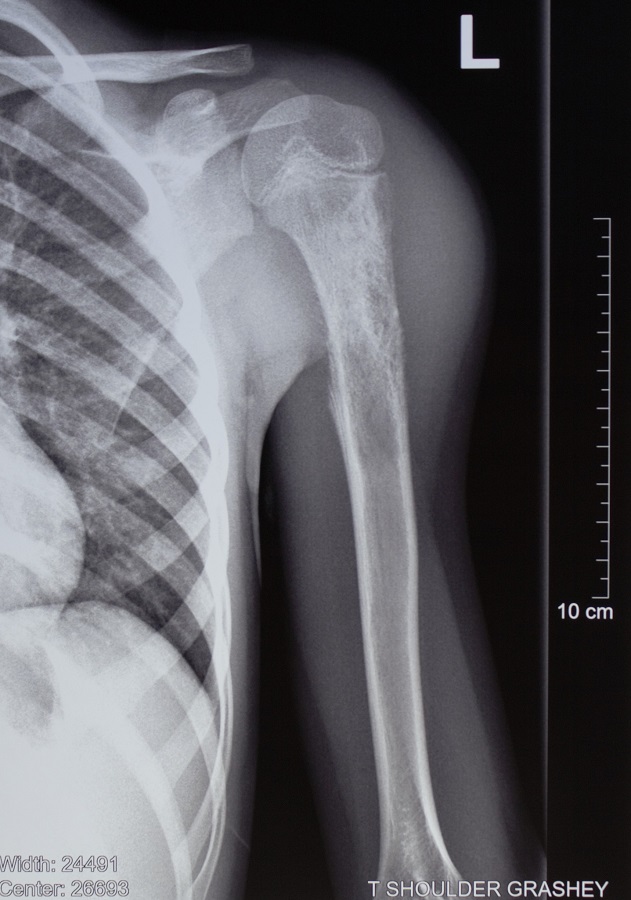

Բազկոսկրի Յուինգի սարկոմա (չարորակ) ունեցող 6-ամյա աղջնակի մոտ վիրահատական միջամտությունից հետո պահպանվել է վերին վերջույթը:

Երեխան նաև քիմիաթերապիայի 7 կուրս է անցել:

Վիրահատությունը Մանկական վնասվածքաբանության և օրթոպեդիայի կլինիկայի ղեկավար, «Մուրացան» ամալսարանական հիվանդանոցի գլխավոր բժշկի տեղակալ Արարատ Նազանյանը կատարել է «Նաիրի» բժշկական կենտրոնի ոսկրային օնկոլոգիայի կլինիկայի ղեկավար Գալուստ Գալստյանի հետ համատեղ: